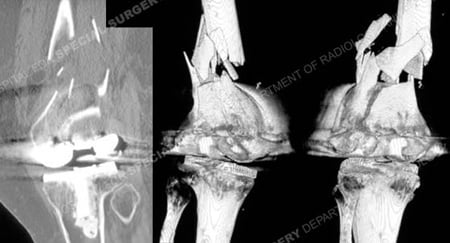

CT scan and 3D CT image revealing periprosthetic femur fracture from a case example presented by the orthopedic trauma service at Hospital for Special Surgery.

CT scan images and 3D CT reconstruction images further delineating the fracture pattern.